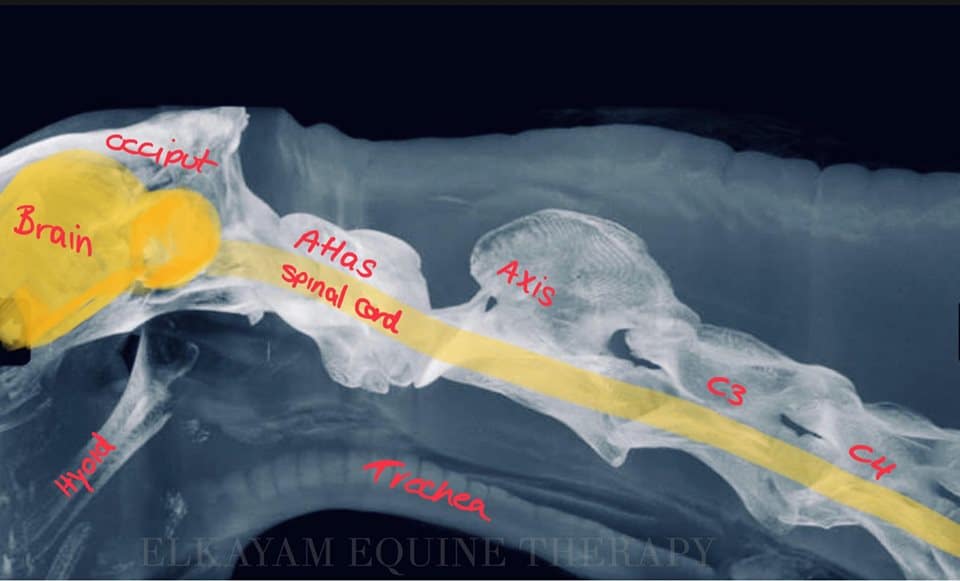

Headshaker diagnosen er meget svær at stille, og desværre også - for rigtigt mange dyrlæger -svær at gøre noget ved. Årsagen til symptomerne er svær at finde og ofte er multifaktoriel...